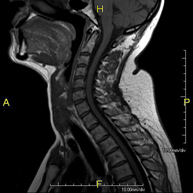

RM Columna Cervical

RM Columna CervicalProva diagnòstica no invasiva que consisteix en l'obtenció d'imatges d'alta definició anatòmica de la columna cervical, mitjançant l'ús d'un camp electromagnètic i ones de ràdio (amb un emissor i un receptor). No utilitza radiació ionitzant. Indicacions: traumatisme, degeneració de la columna i hèrnies.